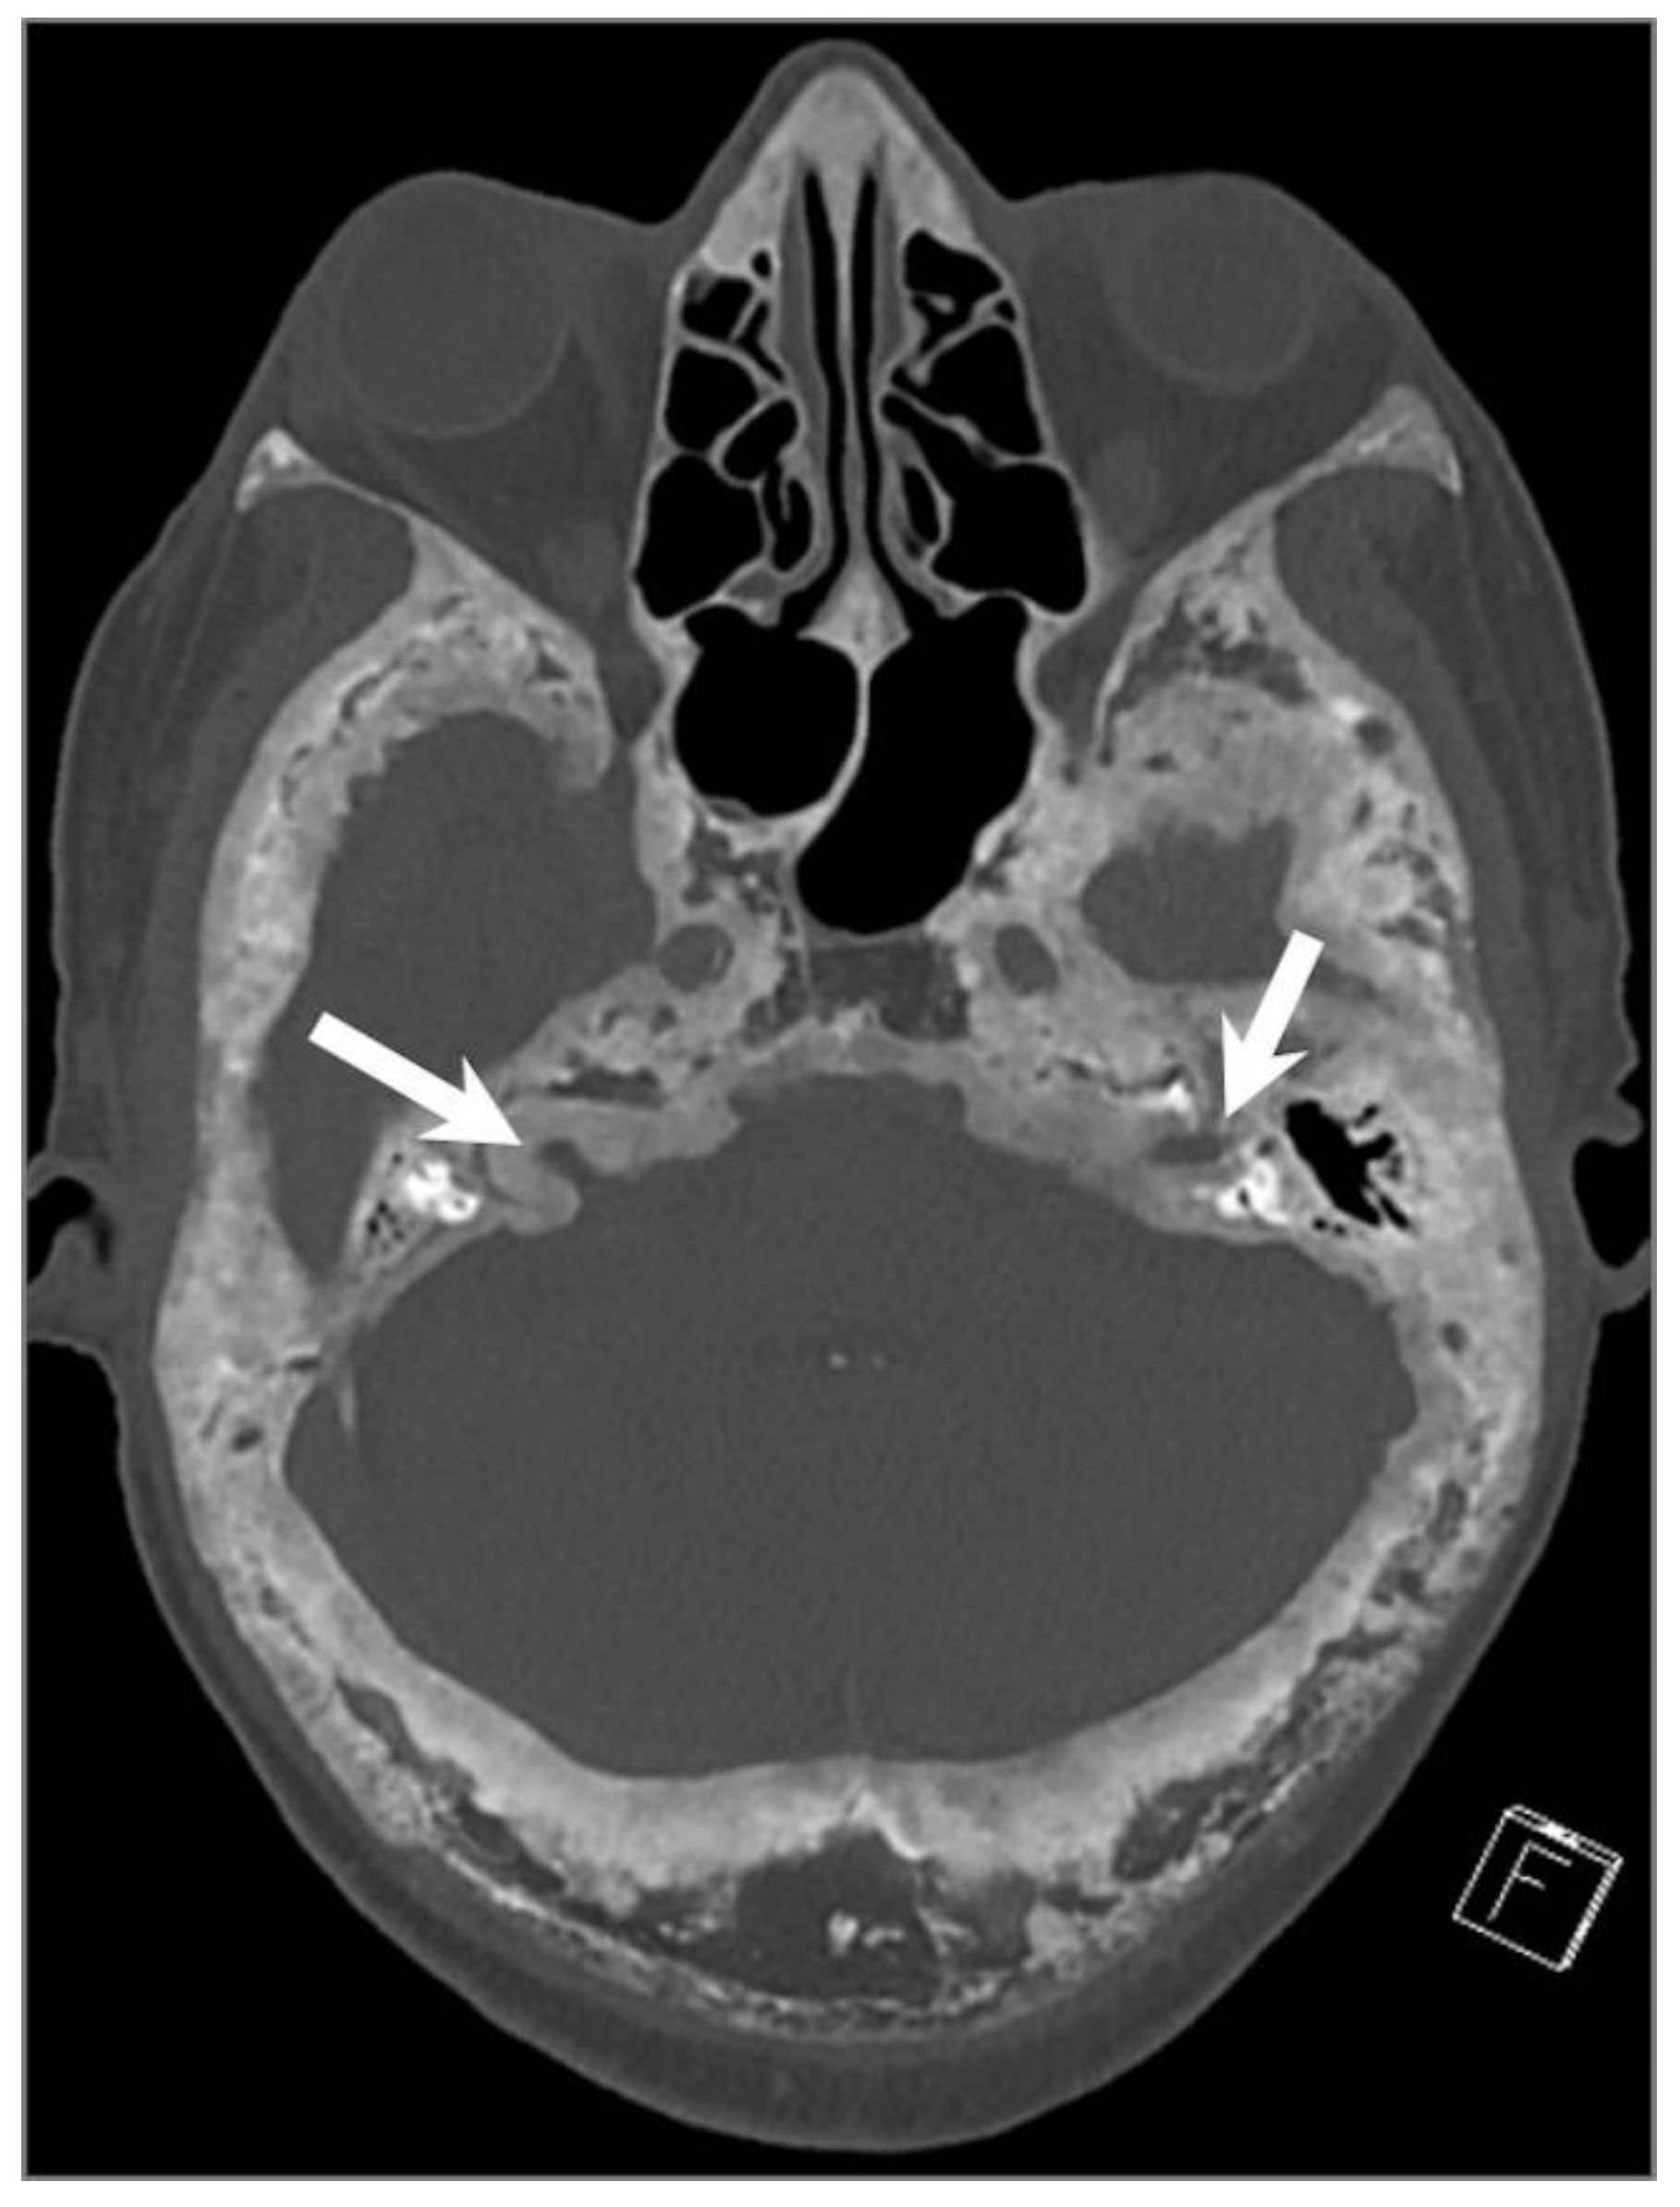

5.11. Giant Aneurysm